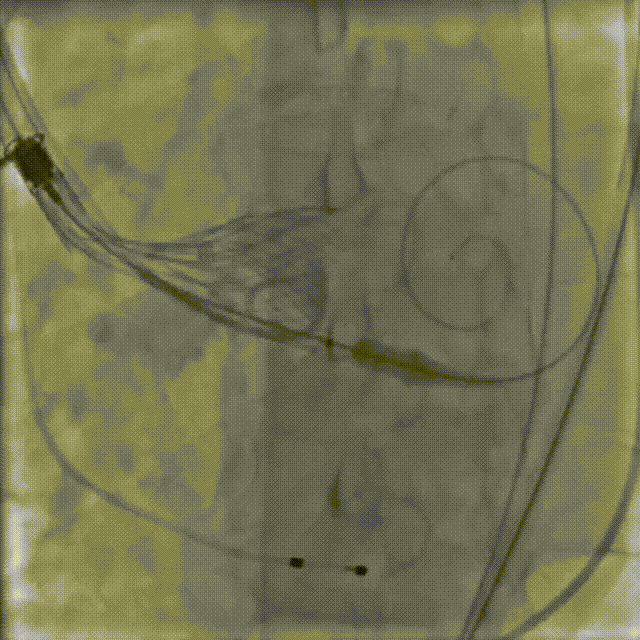

4.VitaFlow liberty™ TAV24瓣膜系统1:1等量精准释放

猪尾巴在无冠窦窦底定位,缓慢释放瓣膜,多次造影评估,实时观察冠脉显影情况.

释放到后1/3,多体位造影评估冠脉及植入深度

5.释放完成

瓣膜释放后造影提示冠脉⽆遮挡

最终瓣膜植入深度可,形态佳,⽆瓣周漏